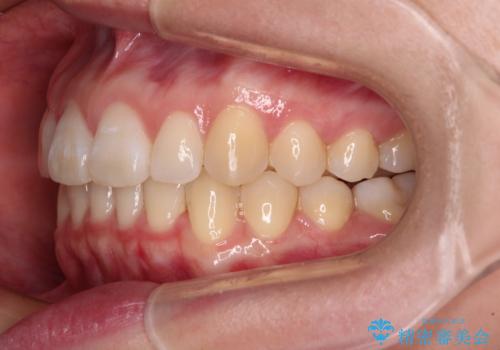

- 上顎前歯の隙間を気にして来院された患者様です。

下顎前歯が上顎前歯に食い込むような咬み合わせにより、上顎前歯が開いてしまっていたため、咬合高径の挙上により突き上げを改善するよう、インビザラインにより矯正治療を行うこととしました。

咬合高径の挙上により上顎前歯の突出感も改善することができ、整った口元となりました。